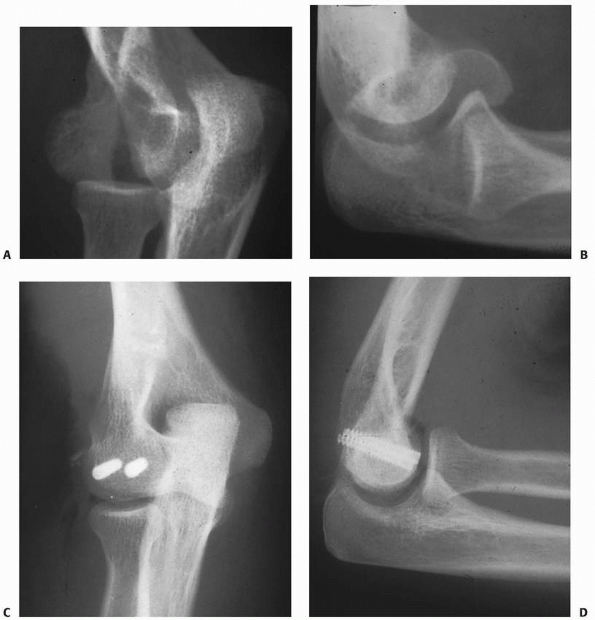

![]() |

FIGURE 15-26 Fracture of the capitellum in a 13-year-old girl. A.

Injury film, lateral view, shows the large capitellar fragment lying anterior and proximal to the distal humerus. Both the radiocapitellar (solid arrow) and trochlear grooves (open arrow) are seen in the fragment. B. In the AP view, only a faint outline of the fragment is seen (arrows). |

FIGURE 15-27 A,B. Fracture of the capitellum in a 14-year-old boy. C,D. After open reduction and fixation with two small cannulated screws through a lateral approach.

|

if an anatomic reduction can be achieved with a minimum of open

manipulation or dissection, then we prefer to reattach it with two

small cannulated screws inserted from posterior to anterior through a

lateral approach. Enough bone must be present in the capitellar

fragment to engage the screw threads, and if possible, countersink the

heads of the screws (see Fig. 15-27). If the

fracture is old, if there is any comminution of the fragment, or if

there is little bone in which to engage the screw threads, we believe

the appropriate treatment is to simply excise the fragment and start

early motion.